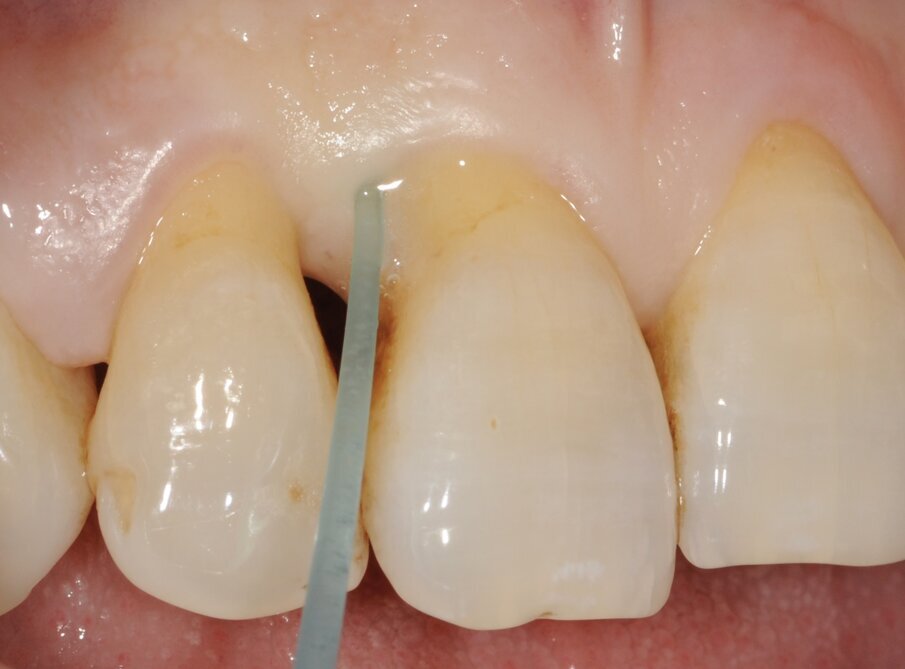

Un paziente di 56 anni non fumatore viene riferito alla nostra osservazione per il trattamento della parodontite. Dopo aver effettuato la diagnosi (parodontite generalizzata Stadio III, Grado C) il paziente è sottoposto a due sedute di scaling sopra gengivale (step 1) e successivamente a 4 sedute di debridement sotto gengivale effettuato con strumenti ultrasonici e manuali (step 2). Al momento della rivalutazione si registra un miglioramento degli indici di placca e di sanguinamento (FMPS e FMBS ≤ 20%) e una riduzione di tutte le tasche parodontali (PD<4 mm) in ciascun sestante a eccezione del secondo sestante. In questa regione si registra una tasca residua con PD = 6 mm a carico dell’elemento 1.1, associata a un riassorbimento osseo radiografico prevalentemente orizzontale (Figg. 1, 2). Considerando il miglioramento di tutti i parametri e degli indici parodontali e la presenza di una tasca con PD = 6 mm a carico di un solo elemento dentario si decide di ritrattare l’elemento 1.1 con terapia non chirurgica (step 3). La nuova ristrumentazione è stata effettuata seguendo il protocollo Clean&Seal che prevede l’associazione di ipoclorito di sodio stabilizzato con amminoacidi e acido ialuronico reticolato ad alto peso molecolare in combinazione con il debridement sotto gengivale. Dopo anestesia locale, è stato applicato all’interno della tasca l’ipoclorito di sodio stabilizzato con amminoacidi e lasciato agire per circa 60 secondi (Fig. 3). Successivamente è stata effettuata la strumentazione sotto gengivale mediante l’utilizzo di strumenti ultrasonici e manuali (Figg. 4, 5). Alla fine della procedura di strumentazione, nella tasca è stata effettuata un’irrigazione con soluzione salina sterile e la procedura di applicazione di ipoclorito di sodio e di strumentazione meccanica è stata ripetuta per 4 volte. Un fattore critico per garantire un risultato migliore è di evitare di instillare qualsiasi soluzione a base di clorexidina nella tasca, in quanto inibisce l’adesione cellulare. Alla fine del trattamento meccanico è stato inserito l’acido ialuronico reticolato ad alto peso molecolare all’interno della tasca per stabilizzare il coagulo e accelerare la guarigione (Fig. 6). Il controllo clinico è stato effettuato dopo 6 settimane dal trattamento con completa chiusura della tasca (Fig. 7).